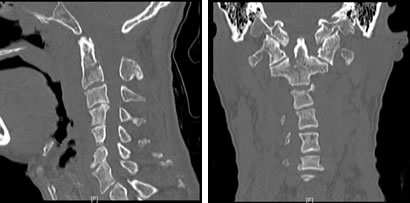

上颈椎的解剖结构非常复杂,周围有众多的主要神经、血管,手术操作时稍有不慎,就可能招致灾难性的后果,加上患者寰椎后弓的发育不全,造成延髓处骨性屏障缺失,以及显露、置钉时的解剖标志丧失,极大地增加了手术的难度以及风险。为保障安全,医院根据患者高精度CT三维扫描的原始数据,依托院外高新科技3D打印实验室,制作出1:1的上颈椎模型,真实还原了患者上颈椎骨折及畸形的情况。根据3D打印模型,骨科团队在陈飞博士的主持下进行多次的模拟手术,在毫米级别上,精确地定位了内固定物的置入点、明确了螺钉的方向、直径和长度,并对手术中可能出现的意外作了充分的估计和预演。

5月8日,决定治疗成败的关键一天到来了。因手术是经后路进行,需要神经外科的特殊头架固定,治疗团队特邀本部神经外科江常震副主任医师指导头架的使用及固定。手术由骨科陈飞博士主刀,历时约5小时,出血仅150ml,麻醉清醒后,病人四肢感觉、运动功能正常,生命体征平稳,表明未损伤颈髓和椎动脉。术后,患者颈部疼痛明显缓解,术后一天就拔除了气管插管,回到普通病房,并可以自行坐起。